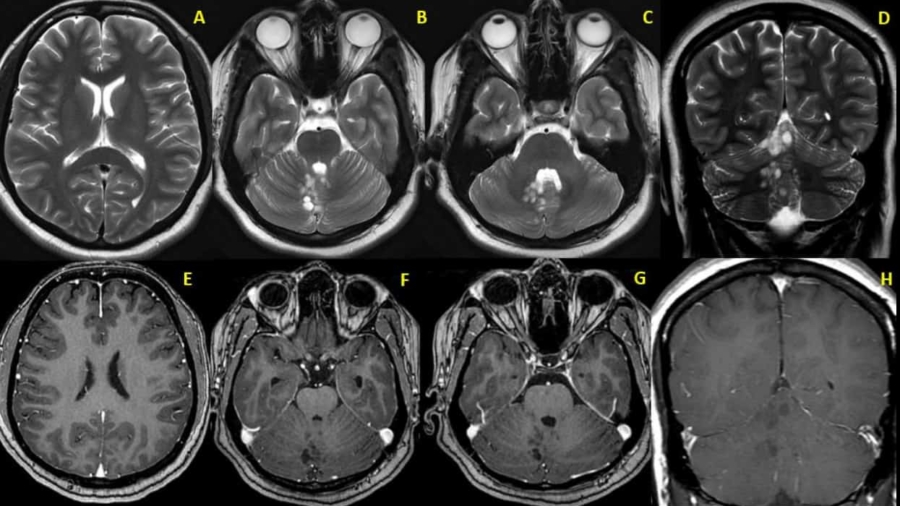

A 71 year old male presented with 1-year history of ocular symptoms (diplopia, proptosis, episcleral congestion).

A 30 year old female with headache. What is the diagnosis?

An elderly male, known diabetic with one episode of seizure. What is the diagnosis?